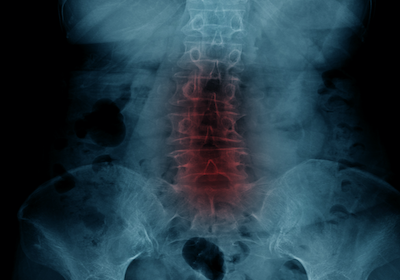

sciatic nerve scan

The Royal Australian and New Zealand College of Radiologists recommends an x-ray or other scanning only when there is significant symptoms.

This includes the following:

• Changes to voiding (bladder or bowel function altered)

• Weakness, numbness and severe pain.

As a result, you can see that pain alone is not a reason to have an investigation.